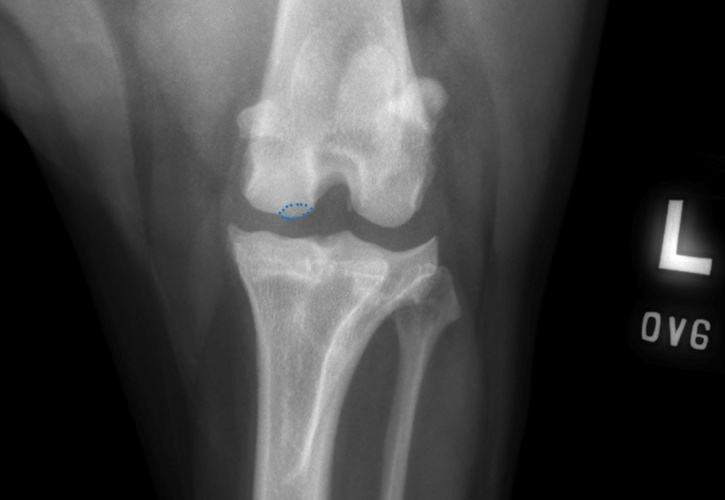

OCD lesion of the canine stifle highlighted with a blue dotted line

Osteochondritis dissecans (OCD) is a developmental condition that arises due to a disturbance in the normal differentiation of cartilage cells resulting in failure of endochondral ossification (essential process during foetal development of skeletal system resulting in bone formation).

In dogs that grow very quickly, the rapid cartilage growth can outstrip its own blood supply causing abnormal cartilage development resulting in lameness, pain and subsequent osteoarthritis. In some cases, flaps of diseased cartilage become separated from the remaining cartilage surface. This is called osteochondritis dissecans.